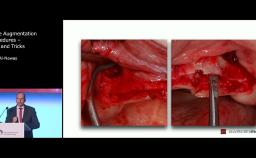

WS2024 - Clinical Procedure: Treatment of Peri-implantitis – Modified Reconstructive Approach

ITI World Symposium 2024 clinical video by Frank Schwarz - part of the "Management of Peri-Implantitis" session.

Substantial evidence suggests that non-surgical therapy has a limited efficacy to arrest disease progression, thus indicating the necessity of a surgical intervention in the majority of patients diagnosed with peri-implantitis. This video will focus on a modified surgical reconstructive therapy of a combined Class 3 peri-imlantitis associated defect.